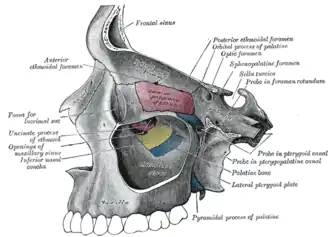

Medial wall of left orbit. (Inferior nasal concha visible in center in yellow.) | |